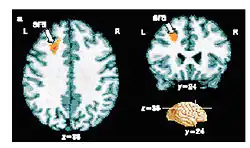

Results from an fMRI experiment in which people made a conscious decision about a visual stimulus. The small region of the brain coloured orange shows patterns of activity that correlate with the decision making process. Crick stressed the importance of finding new methods to probe human brain function.